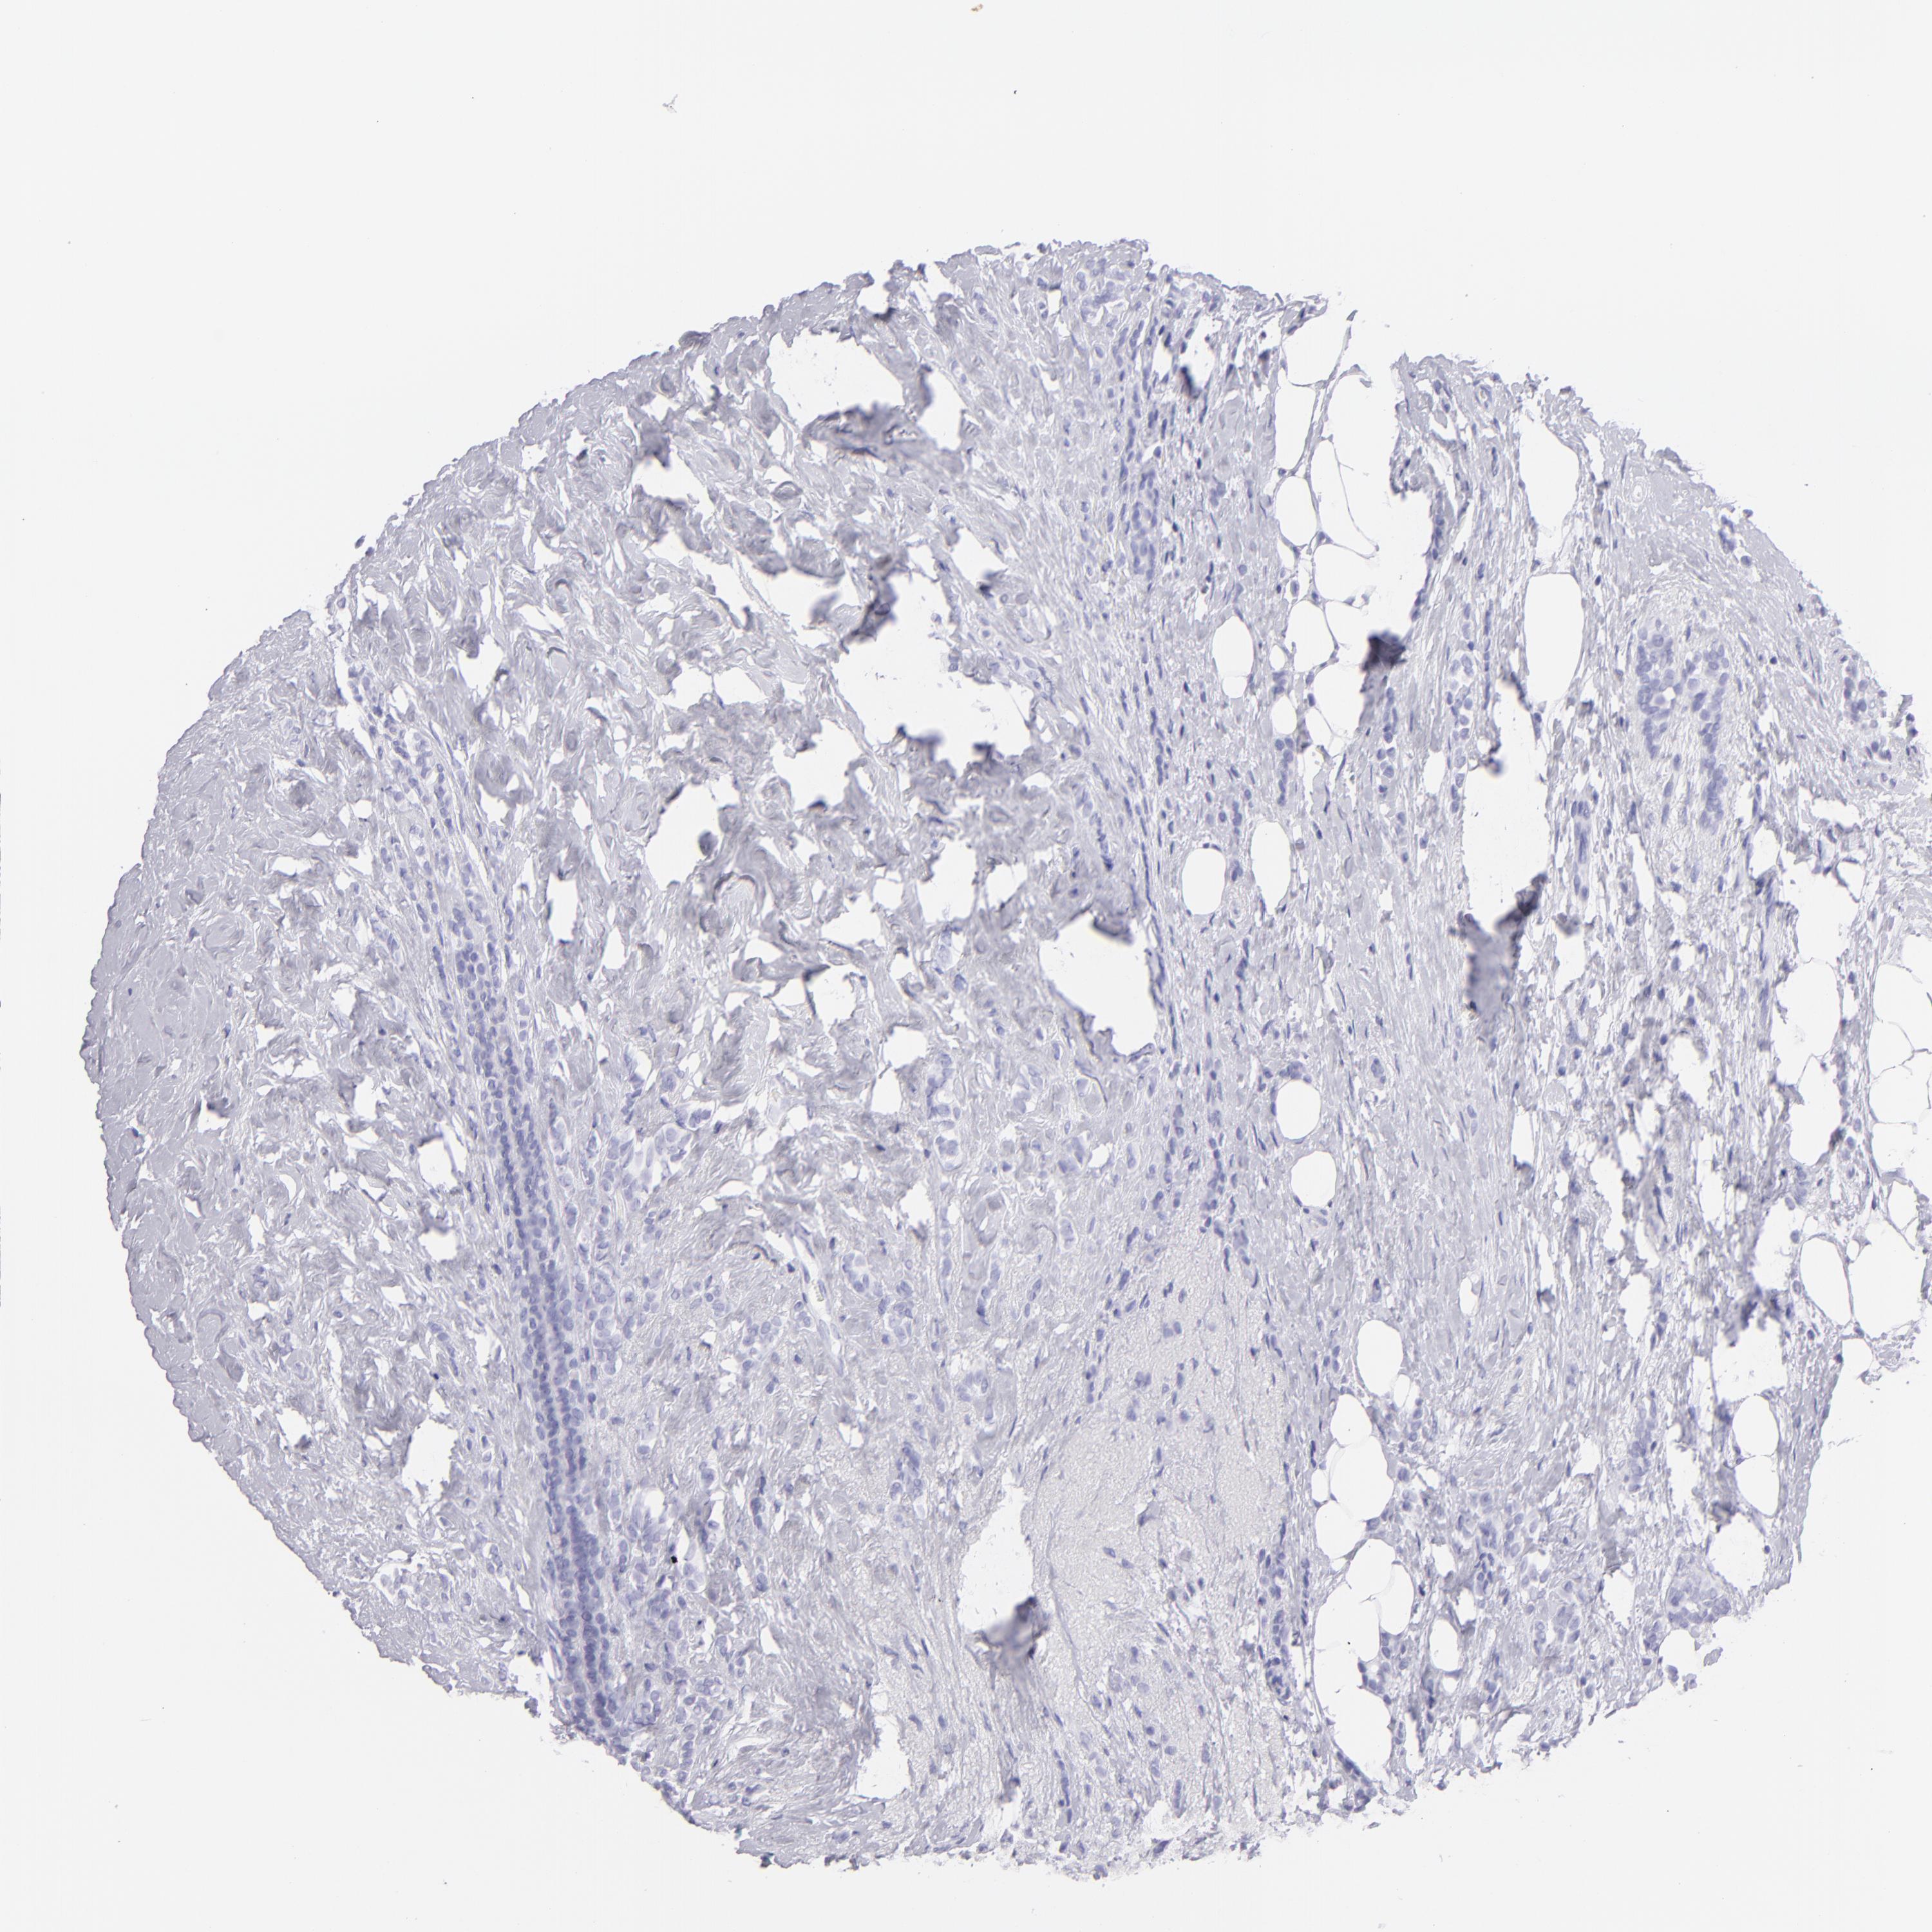

CANCER BREAST CANCER Show tissue menu

BRCA TCGA BRCA VALIDATION PROTEIN EXPRESSION

Breast cancer

Human cancer

Breast invasive carcinoma